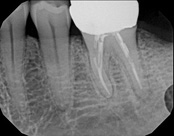

This patient presented with pain when chewing. Diagnostic testing was done and determined it was the lower molar. The diagnosis was: pulpal necrosis, symptomatic periradicular periodontitis. Root canal treatment was performed with laser disinfection. The tooth had a crown and we accessed the tooth through the crown. We saved the tooth and the crown.